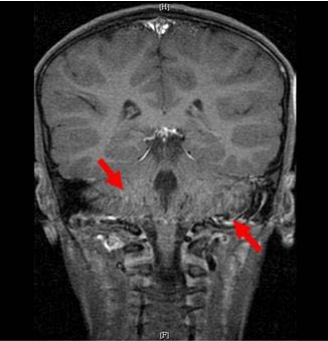

37. 下圖中箭號所指的構造為何?

(A)medulla oblongata (B)pons (C)cerebral peduncle (D)cerebellar peduncle

48.腦部MRI檢查時,顱底血管出現箭號所指之高訊號,最可能的原因為 何?

(A)截斷假影(truncation artifact) (B)反褶假影(aliasing artifact) (C)串擾假影(cross-talk artifact) (D)流動相關增強作用(flow related enhancement)